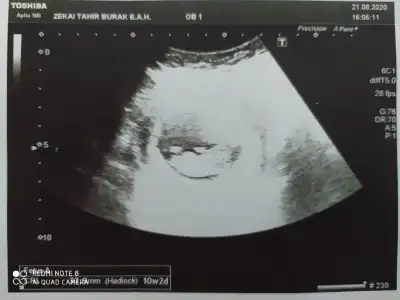

Tek yumurta sanırım ama boyutsuz USG paylaşın benim ikiz kızlarım var 💗💗🥰🥰

Çift yumurta dedi doktorumuz ama bilemiyorum ikiz olduğuna soktayım hala😬 yaa normal ultrasonu almayı unutmusum heyecandan ayrıntılı olanlar var ama 10haftalık var onu paylaşıyorum anlasılır belki😇 ne güzel ikiz kız bakımında zorlandınızmı😅😇 bende ilk hamile olduğumu öğrendiğimde kız hissediyordum ama ikiz olunca bir kız bir erkek gibi geliyor ama gönül öyle istiyor diyede olabilir🙈 sağlıklı olsunlar da ama bi merak oluyor illa işte😊

Eklentiler

• IMG_20200924_131022.webp

IMG_20200924_131022.webp

31,3 KB · Görüntüleme: 56

İkiside kız görünüyor ama bu haftalar yanitir siz 11 12 13 haftalar paylasin